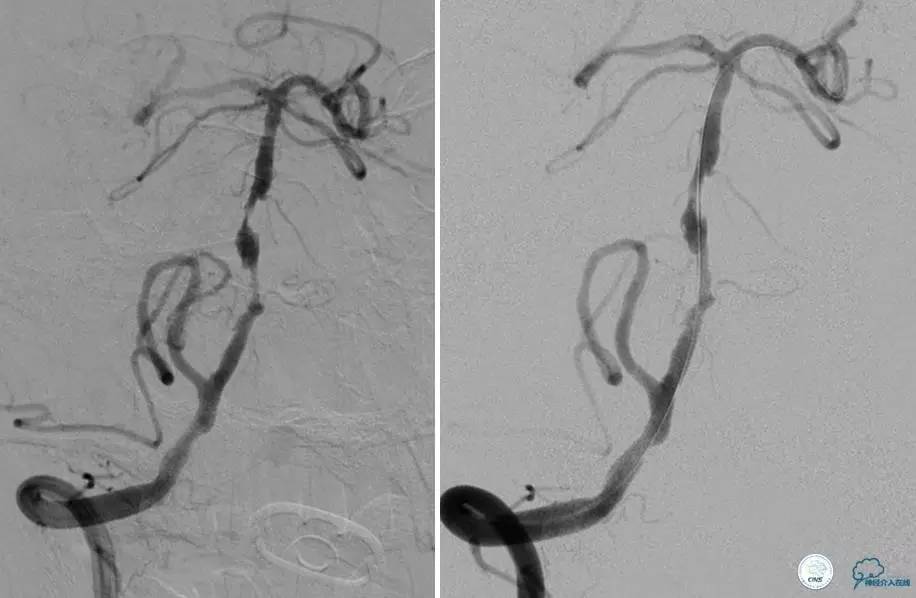

患者:49岁男性,左侧偏瘫1个月,药物治疗、康复训练效果不好,转我院,肌力0~1级。

core-clilnical明显不匹配,是介入开通的合适患者。

造影评价血管、判断闭塞段,微导丝谨慎穿过闭塞段,微导管造影,交换技术,球囊扩张,Enterprise支架。在后扩张时导丝刺破M3段血管,蛛网膜下腔出血(SAH)。

微导管进入破裂血管,栓塞弹簧圈1枚,出血停止,结束手术。继续双抗,术后2天肌力2级,神经功能恢复明显加快。

术后即刻和6天后CT,患者无明显临床症状。

半年后复查造影,无支架内再狭窄,可见弹簧圈,患者恢复至自己柱杖行走。